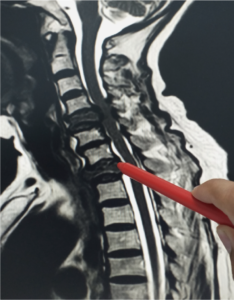

Cervical Radiculopathy & Myelopathy

The spine, also called the back bone, is designed to give us stability, smooth movement, as well as providing a corridor of protection…